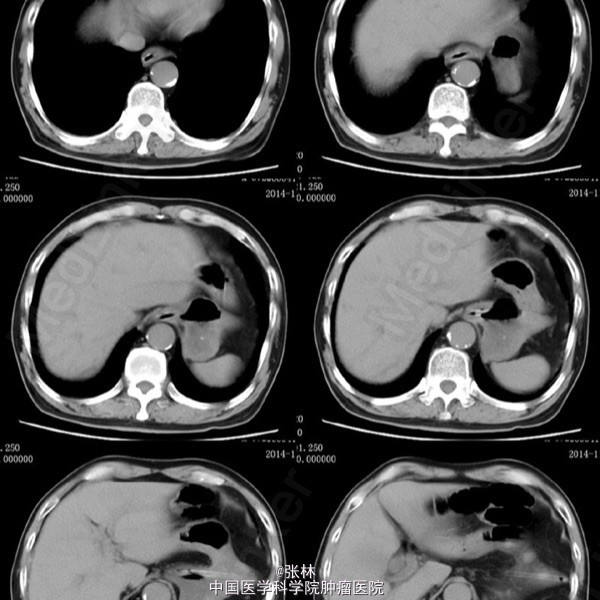

男性,72岁。 主诉:突发腹痛、腹胀伴呕吐1天。 现病史:患者1天前无诱因感全腹部疼痛,呈阵发性绞痛,无放射痛,疼痛开始不剧,伴有畏寒,呕吐胃内容物1次,量约30ml。遂到我院门诊就诊,考虑为急性胃肠炎,予抗炎、解痉护胃等支持治疗,症状未见好转,并进行性加重而入住我科。 专科检查:全腹稍胀,未见肠型及蠕动波,无上腹搏动。腹软,中下轻压痛,无反跳痛。全腹未及肿块,肠鸣音活跃,7次/分。 术中所见:探查见异物位于回肠距回盲部约50cm,大小约8*3*2cm,堵塞肠管,近端肠管充血水肿明显,肠管扩张最大处直径约8cm,未见浆膜层破裂损伤等,系膜无扭转,有少许渗液,探查全部小肠未及肿物腹腔内可见中等量黄色积液,稍浑浊,网膜及腹膜有少量脓苔。洗净腹腔内积液,于肿物边缘对肠系膜缘纵行切开约2cm,取出异物,为半个大小约8*3*2cm的冬菇。